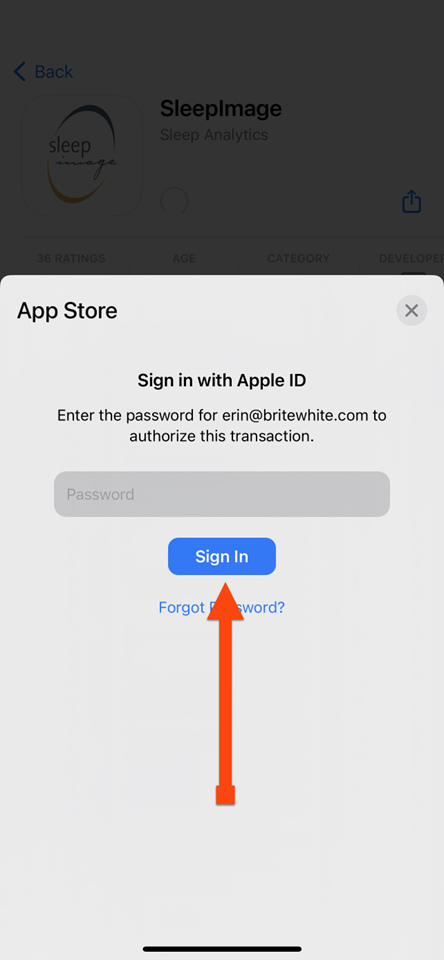

SLEEPIMAGE APP (iPhone)

SLEEPIMAGE APP (iPhone)

SLEEPIMAGE APP (iPhone)

SLEEPIMAGE APP (iPhone)

SLEEPIMAGE APP (iPhone)

SLEEPIMAGE APP (iPhone)

SLEEPIMAGE APP (iPhone)

SLEEPIMAGE APP (iPhone)

SLEEPIMAGE APP (iPhone)

SLEEPIMAGE APP (iPhone)

SLEEPIMAGE APP (iPhone)

SLEEPIMAGE APP (iPhone)

SLEEPIMAGE APP (iPhone)

SLEEPIMAGE APP (iPhone)

SLEEPIMAGE APP (iPhone)

SLEEPIMAGE APP (iPhone)

SLEEPIMAGE APP (iPhone)

SLEEPIMAGE APP (iPhone)

SLEEPIMAGE APP (iPhone)

SLEEPIMAGE APP (iPhone)

SLEEPIMAGE APP (iPhone)

SLEEPIMAGE APP (iPhone)

SLEEPIMAGE APP (iPhone)

SLEEPIMAGE APP (iPhone)

SLEEPIMAGE APP (iPhone)

SLEEPIMAGE APP (iPhone)